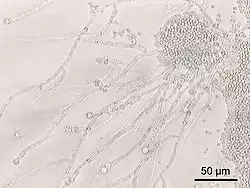

| Candida albicans at 200× magnification | |